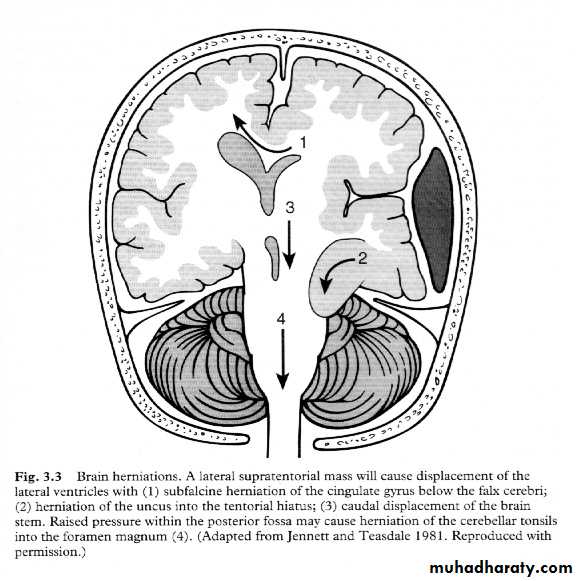

7. Cerebral Herniation

a. Subfalcine Herniation

b. Uncal Herniation

c. Tentorial Herniation

d. Tonsillar Herniation

Neurosurgery